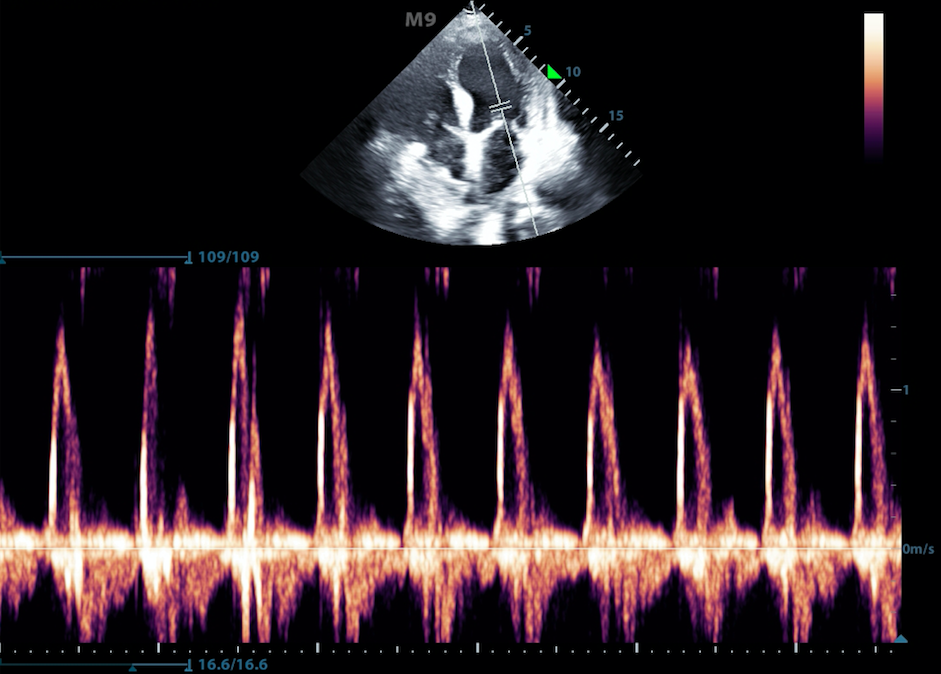

- M-mode (motion mode) captures returning echoes in only one line of the B-mode image displayed over time

- Movement of structures positioned in that line can now be visualized

- Often M-mode and B-mode are displayed together in real-time on the ultrasound monitor (Figure 2, Video 1)

- Figure 2. M-Mode (lower portion of the image) combined with B-Mode image. In this still image the M-mode captures the movement of a particular part of the heart.)

Video 1. M-Mode showing movement of the mitral valve